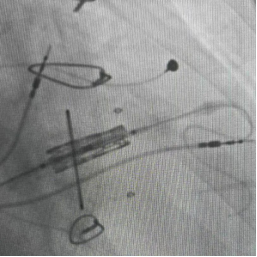

球囊擴張術

三尖瓣置換術

永久起搏器植入術“這相當于用微創的方式,完成過去需要三次手術才能解決的問題。”陳文生主任解釋說,介入操作無需再次開胸,只需通過血管穿刺送入導管,對患者創傷小,尤其適合這種多次手術后的高危患者。

手術臺上,心臟大血管外科陳文生團隊通過細致的影像引導,將球囊送至原有瓣膜處進行擴張,隨后將新的生物瓣精準釋放在預定位置 。最后,在心臟穩定的狀態下,順利植入了永久起搏器。整個過程中,患者生命體征平穩。